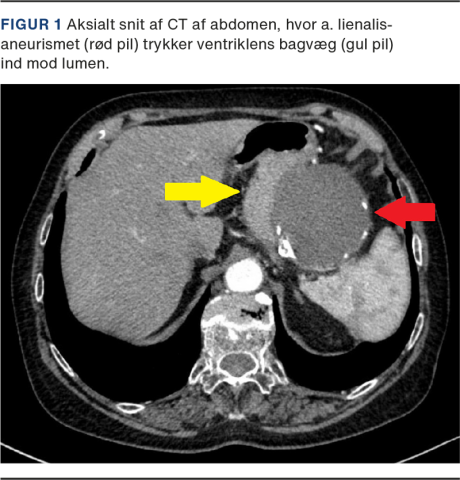

Man valgte at bestille en CT af abdomen mhp. visualisering af bagvedliggende patologi. CT’en viste et gigantisk a. lienalis-aneurisme på 9 cm (Figur 1). Patienten blev efterfølgende henvist til karkirurgerne, som foranstaltede coiling (endovaskulær embolisering) af aneurismet.

En 78-årig tidligere sund og rask kvinde blev henvist til gastroskopi i kræftpakkeforløb grundet tyngdefornemmelse i epigastriet gennem tre måneder. Hun havde ingen smerter. Man foretog gastroskopien, som viste tre Forrest III-ulcera og gastrit. Under gastroskopien bemærkede man, at ventriklens bagvæg nær fundus gastricus bulede ind mod lumen, til trods for at ventriklen var blæst godt op. Impressionen dækkede et område på ca. 7 cm og forsvandt, når man desufflerede. Der var ingen pulsation i impressionen. Overliggende slimhinde var upåfaldende ud over gastrit, som i resten af ventriklen.